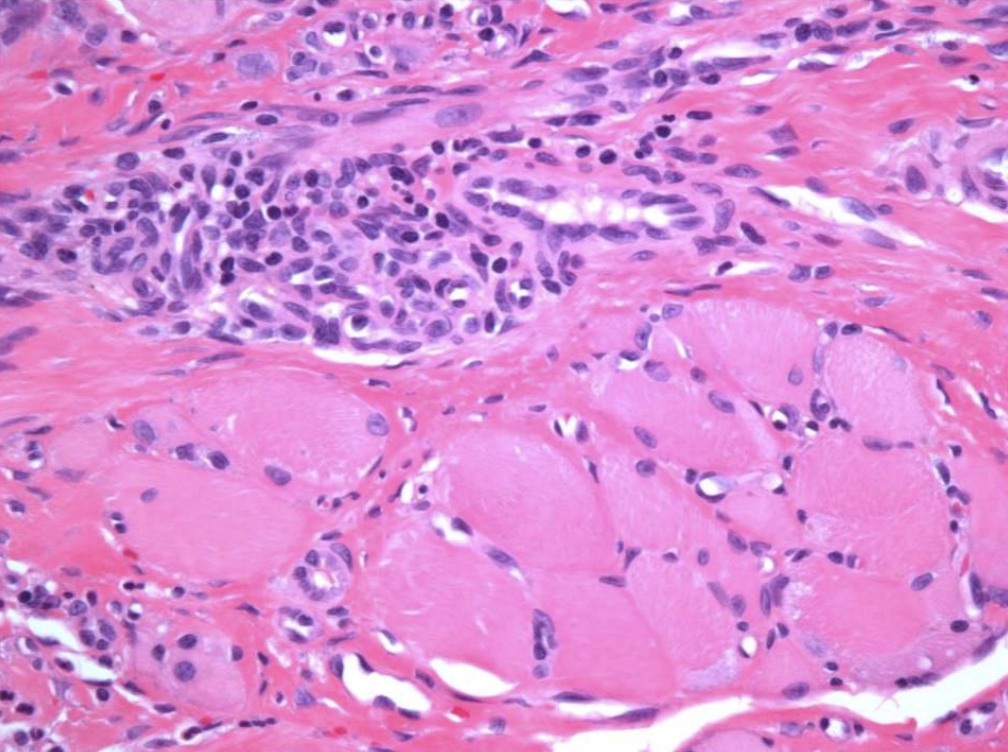

what is this

verruciform xanthoma